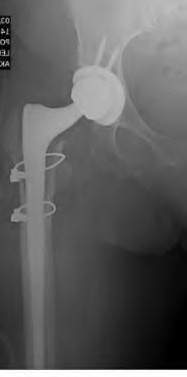

An 82-year-old woman falls and sustains the fracture shown in figure A. She denies any history of dislocation or prodromal pain prior to her fall. What is the most appropriate treatment?

The radiograph demonstrates a periprosthetic femur fracture extending to the tip of the stem. The long spiral fracture is consistent with a loose implant. The bone stock is sufficient. Therefore, this fracture pattern would classify as a B2 using the Vancouver classification system. The Vancouver classification for periprosthetic femoral fractures is simple yet incorporates all the pertinent factors such a location, stem fixation, and bone stock. Type A is a trochanteric fracture- lesser or greater. These can be treated non-operatively usually and ORIF if symptomatic. Type B fractures are around or just below the stem and are subdivided into three types. Type B1 is a fracture with a well fixed stem.

The treatment is cable plating or allograft struts or a combination of the two. Type B2 is a fracture with a loose stem with good bone stock. The treatment is a cementless porous coated long stem atleast two diameter length past the

fracture site. Type B3 is a fracture with a loose stem and comminution. For younger patients, use cementless porous coated long stems with allograft struts. For older patients, consider a tumor prosthesis. Cement fixation is sometimes necessary Type C is a fracture well below the stem tip. These can be treated independently of the prosthesis.

Springer et al showed optimal outcomes with revision involving long extensively-coated femoral stems for Vancouver B fractures.

Masri et al review the classification and treatment of periprosthetic femur fractures.

A 72-year-old male presents 2 years status post fixation of an impending pathologic right femur fracture due to metastatic renal cell carcinoma. He is minimally ambulatory due to pain. Despite radiation therapy, there has been progression of the lesion with extensive cortical bone loss, which is shown in Figure A. A proximal femoral replacement arthroplasty is performed without complications, and is demonstrated in Figure B. Which of the following is true regarding this patients post-operative course?

Figure A shows a lytic lesion of the proximal femur with an intramedullary implant. Figure B shows a proximal femoral replacement.